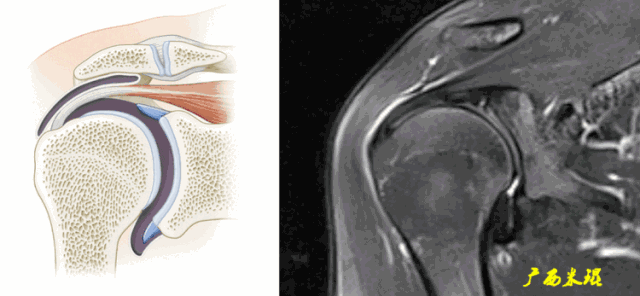

(2)斜矢状位:垂直于冈上肌长轴,观察肩峰形态及喙肩弓,观察肩袖4个组分的短轴断面。

c.钩状肩峰,发生肩袖撕裂的机会大,但绝不是百分之百。

d.肩峰骨刺,发生肩袖撕裂的机会比钩状肩峰还要大,必须认真阅看,肩峰骨刺在斜矢状位上显示得非常清楚。

肩峰骨刺在斜冠状位上能够看到,应该认真观察并且留意其对应的肩袖面。